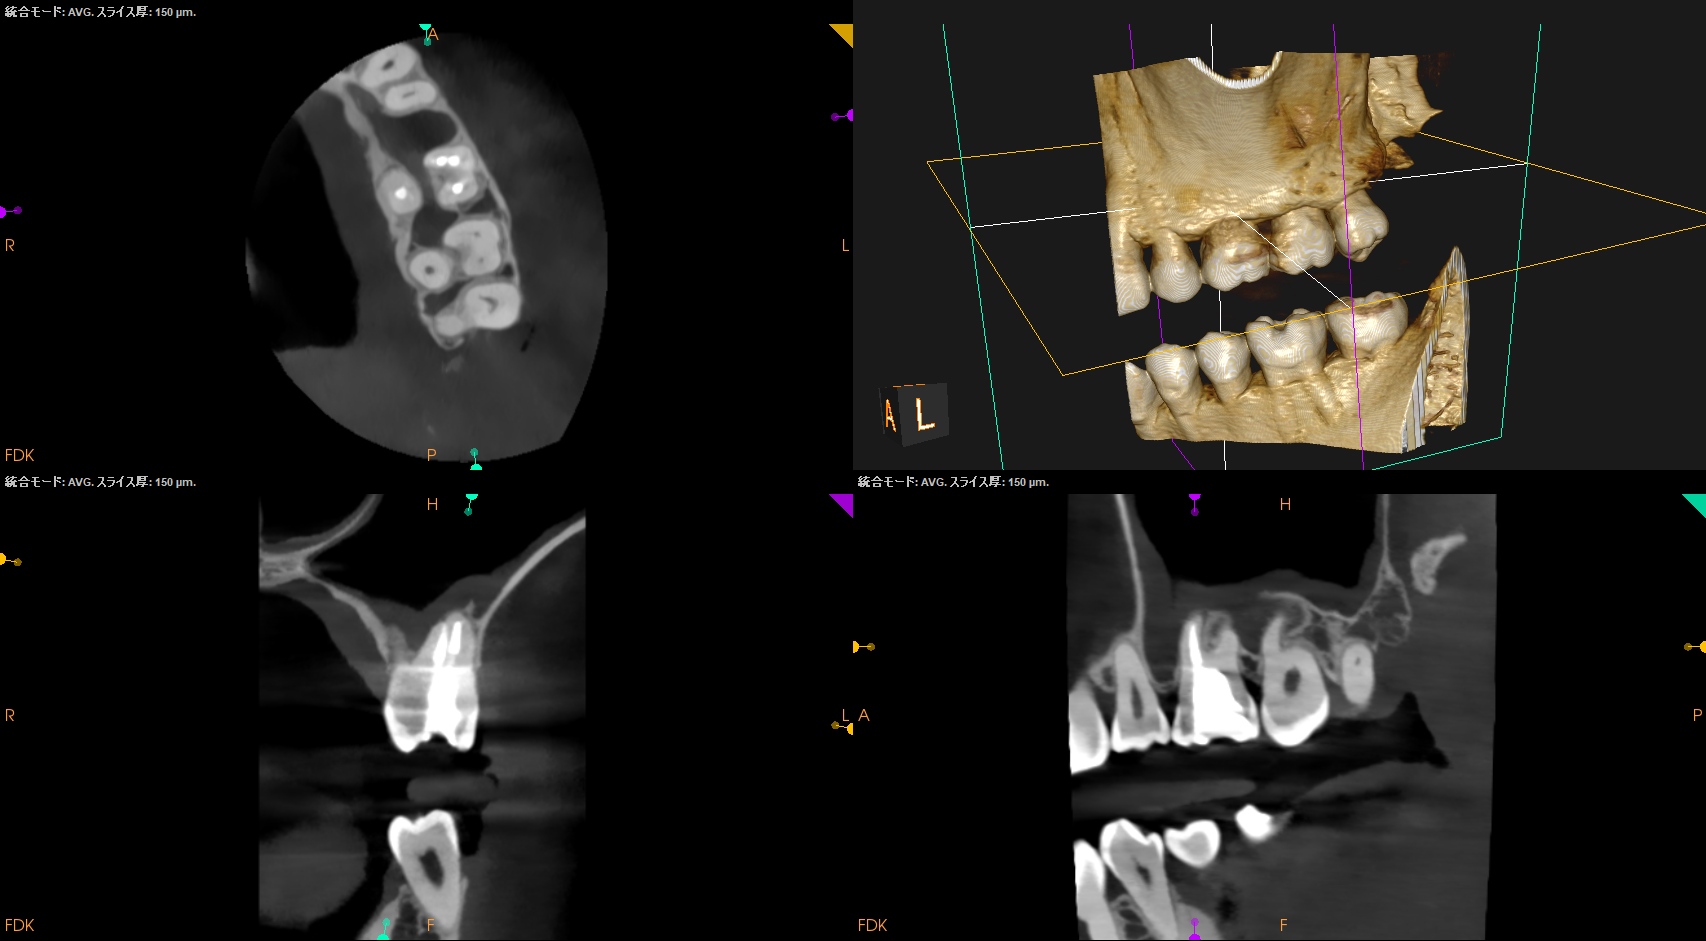

#14 Re-RCT 6yr recall(2026.1.27)

MB

MB2

DB

P

根尖病変は消失した。

また、再治療直後に根尖孔外へとはみ出たGutta Percha Pointの残渣も消失した。